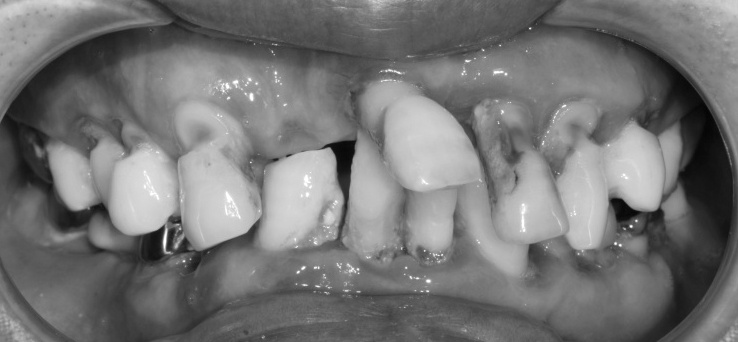

비장한 눈빛을 한 40대 남성분이 치과에 오셨습니다.

치아 상태가 다 안 좋아요.

다 뽑아야 할 것 같아요.

입안 상태를 보니 살릴 수 있는 치아가 하나도 안 보일 정도로 많이 손상되어 있었습니다.

그로 인해 얼마나 고통스러우셨을지 가늠이 되지 않았습니다.

이제 안 좋은 치아들, 그리고 거기에 붙어있는 염증조직들 그리고 세균 덩어리들 모두 제거한 뒤 임플란트 치료를 통해서 깨끗하고 가지런한 치아로 만들어드리기로 했습니다.